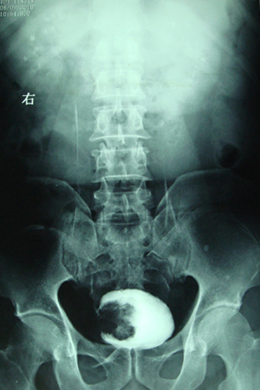

典型病例,男,56岁。无痛性血尿3月。

膀胱占位性病变,呈菜花状生长,考虑膀胱癌。 期待病理。